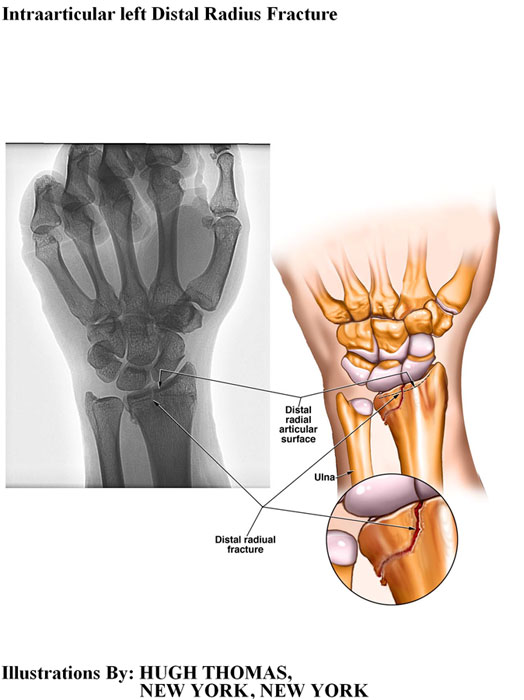

The medical illustrations on this page are examples of the details the attorneys at the Law Offices of William Cafaro prepare for jury presentations.